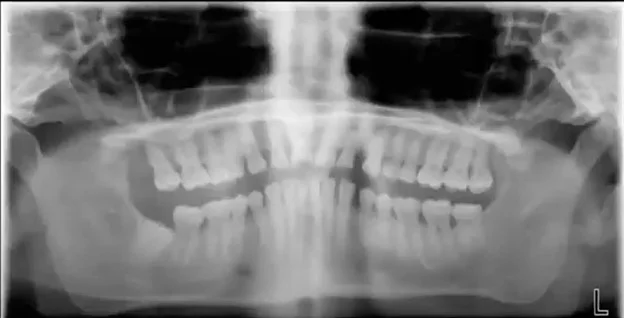

Cloudy artifact down the center of the radiograph

This artifact most commonly looks like a cloudy fuzz down the center of the panoramic radiograph.

This is typically caused when the patient’s spine is “hunched”, or sometimes referred to as “goosenecked” vs. being erect or, even better, stretched.

If the spine is hunched, it means the x-ray must travel through more bone before it reaches the anterior teeth which can result in much less energy to exposing this region of the anatomy. This can result in the cloudiness seen down the center of the radiograph.

The most effective technique to remove this artifact is to have the patient hold the grab bars on the unit and move their feet forward so that the patient is in a “leaning back” position. While this is the ideal approach, we also have seen that this can be easier said than done with some patients (e.g. an elderly patient that cannot hold themselves in this position, and may have an inherent hunch in their spine). Therefore, even if the patient cannot be positioned in this leaning back manner, simply helping the patient to stand as erect as possible will help reduce this anterior artifact.